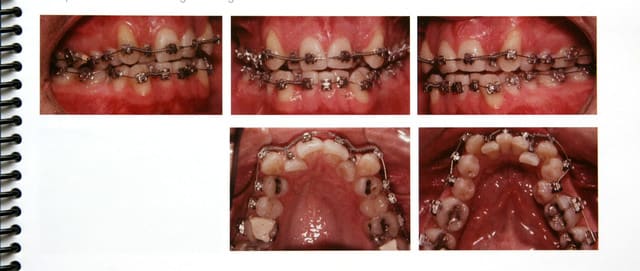

Encore un cas facile, mais sur adulte (43 ans)

Pour vous amuser !

si tes photos sont prises avec le même angle de vue ?? il faut constater une très importante inclinaison des incisives supéieures ..avanvées et torquées ?? ou je me trompe ?.

2 petits trucs qui m'embétent:

Ces cas sont à qui???? A toi Bjc ou dans les docs fournies par devil?

Ensuite y'a comme un truc collé aux dents du patient "fini".... ts ts ts c'est pas joli de tricher, si un cas est stable fonctionnellement y'a pas besoin de contention, langue, lévres, joues et occlusion devraient assurer l'equilibre de tout ça....